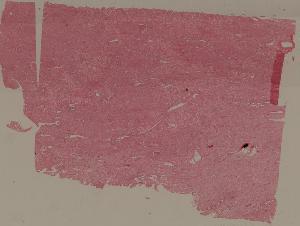

76. Acute pyelonephritis